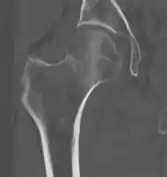

В большинстве случаев достаточно выполнения рентгенограммы в прямой проекции. В ситуациях, когда есть подозрение на перелом шейки бедра, но оно не выявлено на рентгеновском снимке, следующим методом исследования является КТ. В редких случаях для подтверждения диагноза используется МРТ - диагностика.

Случай, демонстрирующий возможный порядок исследования изначально незаметных проявлений:

Заключение о виде перелома делается обычно на основании рентгенограмм во фронтальной проекции или КТ-картины.